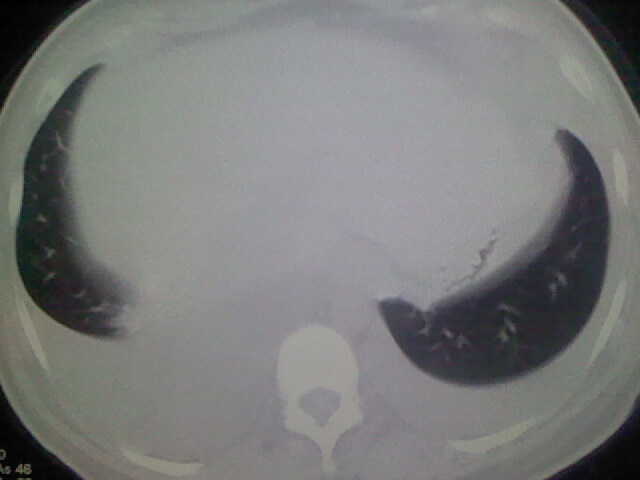

女,24,剖腹产后,突觉胸痛,干咳,不能平卧

做个增强的 ct吧 pte(肺血栓栓塞)不能除外啊 在结合心电图 看看v1-v4导连的t波及st段改变。

患者允许的情况下建议进行心脏超声检查

急性心衰可能,肺梗塞??我没看到病变的具体位置,楼上的给讲讲啊

考虑肺梗塞 双侧胸腔积液 心影增大 建议进一步检查吧

双肺水肿,双侧胸腔积液,肺梗死不能排除